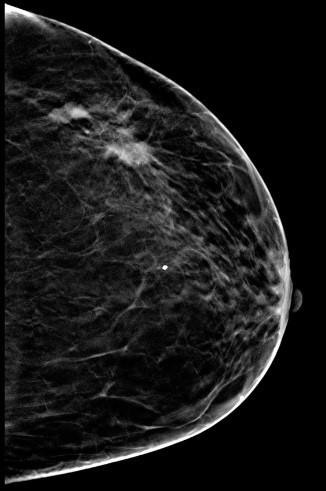

病史:患者,女,59岁,左乳肿块2月余。

2D图像:

常规2D图像MLO位和CC位外上象限见局限密度增高影,其内似见钙化影,在DBT的薄层图像上观察病变范围比2D图像的范围要大些,病变周边见长短不一毛刺,其内见多个细点样钙化影。

左乳局限致密伴钙化,BI-RADS 4C 。